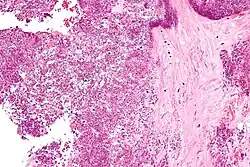

Micrograph showing crystal deposition in an intervertebral disc. H&E stain.

Arthrocentesis, or removing synovial fluid from the affected joint, is performed to test the synovial fluid for the calcium pyrophosphate crystals that are present in CPPD. When stained with H&E stain, calcium pyrophosphate crystals appears deeply blue ("basophilic").[10][11] However, CPP crystals are much better known for their rhomboid shape and weak positive birefringence on polarized light microscopy, and this method remains the most reliable method of identifying the crystals under the microscope.[12] However, even this method has poor sensitivity, specificity, and inter-operator agreement.[12]